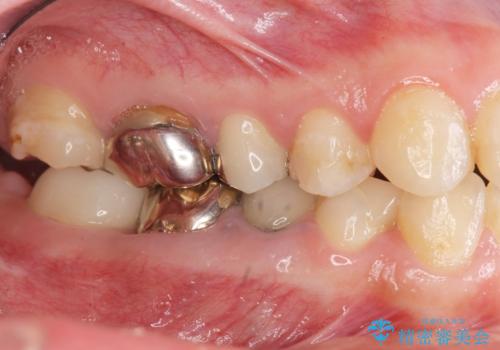

- 虫歯が多く、全体的な歯の検診を希望され当院に来院されました。

X線写真検査より、クラウンや銀歯の下で歯に大きな虫歯が発生し、抜歯を余儀なくされる状況でした。

虫歯に伴い歯槽骨の吸収も見られたので造骨後、インプラントを用いて咬合機能を回復します。